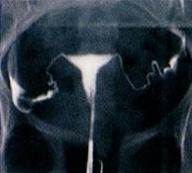

Àڱà ³ªÆÈ°ü Á¶¿µ °Ë»ç

ÀÚ±ÃÀ¯Âø, ÀڱñâÇü, Àڱð³» Á¾¾ç ¹× ³ªÆÈ°üÀÇ ¸·Èû µîÀ» È®ÀÎÇÏ´Â °Ë»çÀÔ´Ï´Ù.

Àڱó°üÁ¶¿µ °Ë»ç ¹æ¹ý

| Àڱó°üÁ¶¿µ ÃÊÀ½ÆÄ | ³ªÆÈ°ü X¼± Á¶¿µ¼ú | |

|---|---|---|

| ½Ã¼ú½Ã±â | »ý¸® Á¾·á ÈÄ 2~3ÀÏ À̳» | |

| ¹æ»ç¼±³ëÃâ | X | O |

| ÅëÁõ | X | O |

| º¸ÇèÀû¿ë | X | O |

| ½Ã¼ú½Ã°£ | 10~20ºÐ | 1½Ã°£ |

| ³»¸·¿ëÁ¾Áø´Ü | ½±´Ù | ¾î·Æ´Ù |

|  |  | |